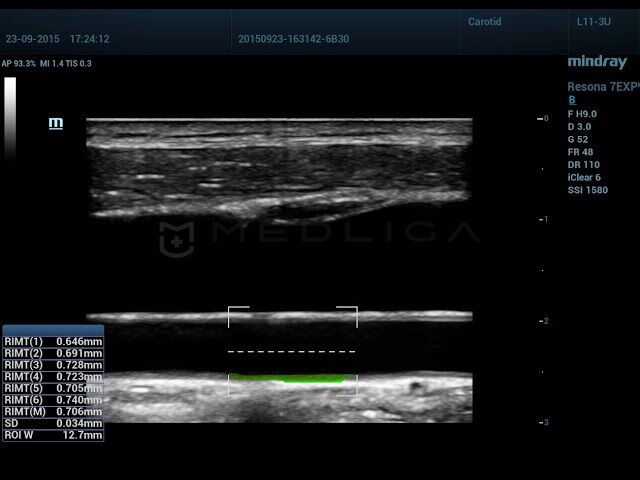

RIMT

Автоматическое измерение комплекса интима-медиа - удобный инструмент для специалиста ультразвуковой диагностики. Mindray делает использование этой функции еще более комфортной, обеспечивая высокую точность измерений.

Определение размера КИМ - основной маркер для определения риска сердечно-сосудистых патологий. Практически все разработчики УЗИ сканеров вносят в функционал оборудования автоматические и ручные алгоритмы для измерения толщины стенки сонной артерии. Для осуществления измерений IMT применяется постобработка кинопетли, что в свою очередь имеет некоторые ограничения. Mindray разработали технология RIMT, с инновационными алгоритмами обработки полученных данных сканирования и гарантирует точное измерение комплекса интима-медиа.

Сравнение технологии RIMT и обычного режима IMT

- RIMT - новейшая технология и в разы превосходит традиционные измерения, например, точность RIMT выше в 16 раз, так как при RIMT происходит измерение ИМТ 6 сердечных циклах, а не 1 как при обычном IMT.

- RIMT (M) - средний показатель за 6 циклов

- SD - стандартное отклонение

- ROI W - ширина исследуемой области